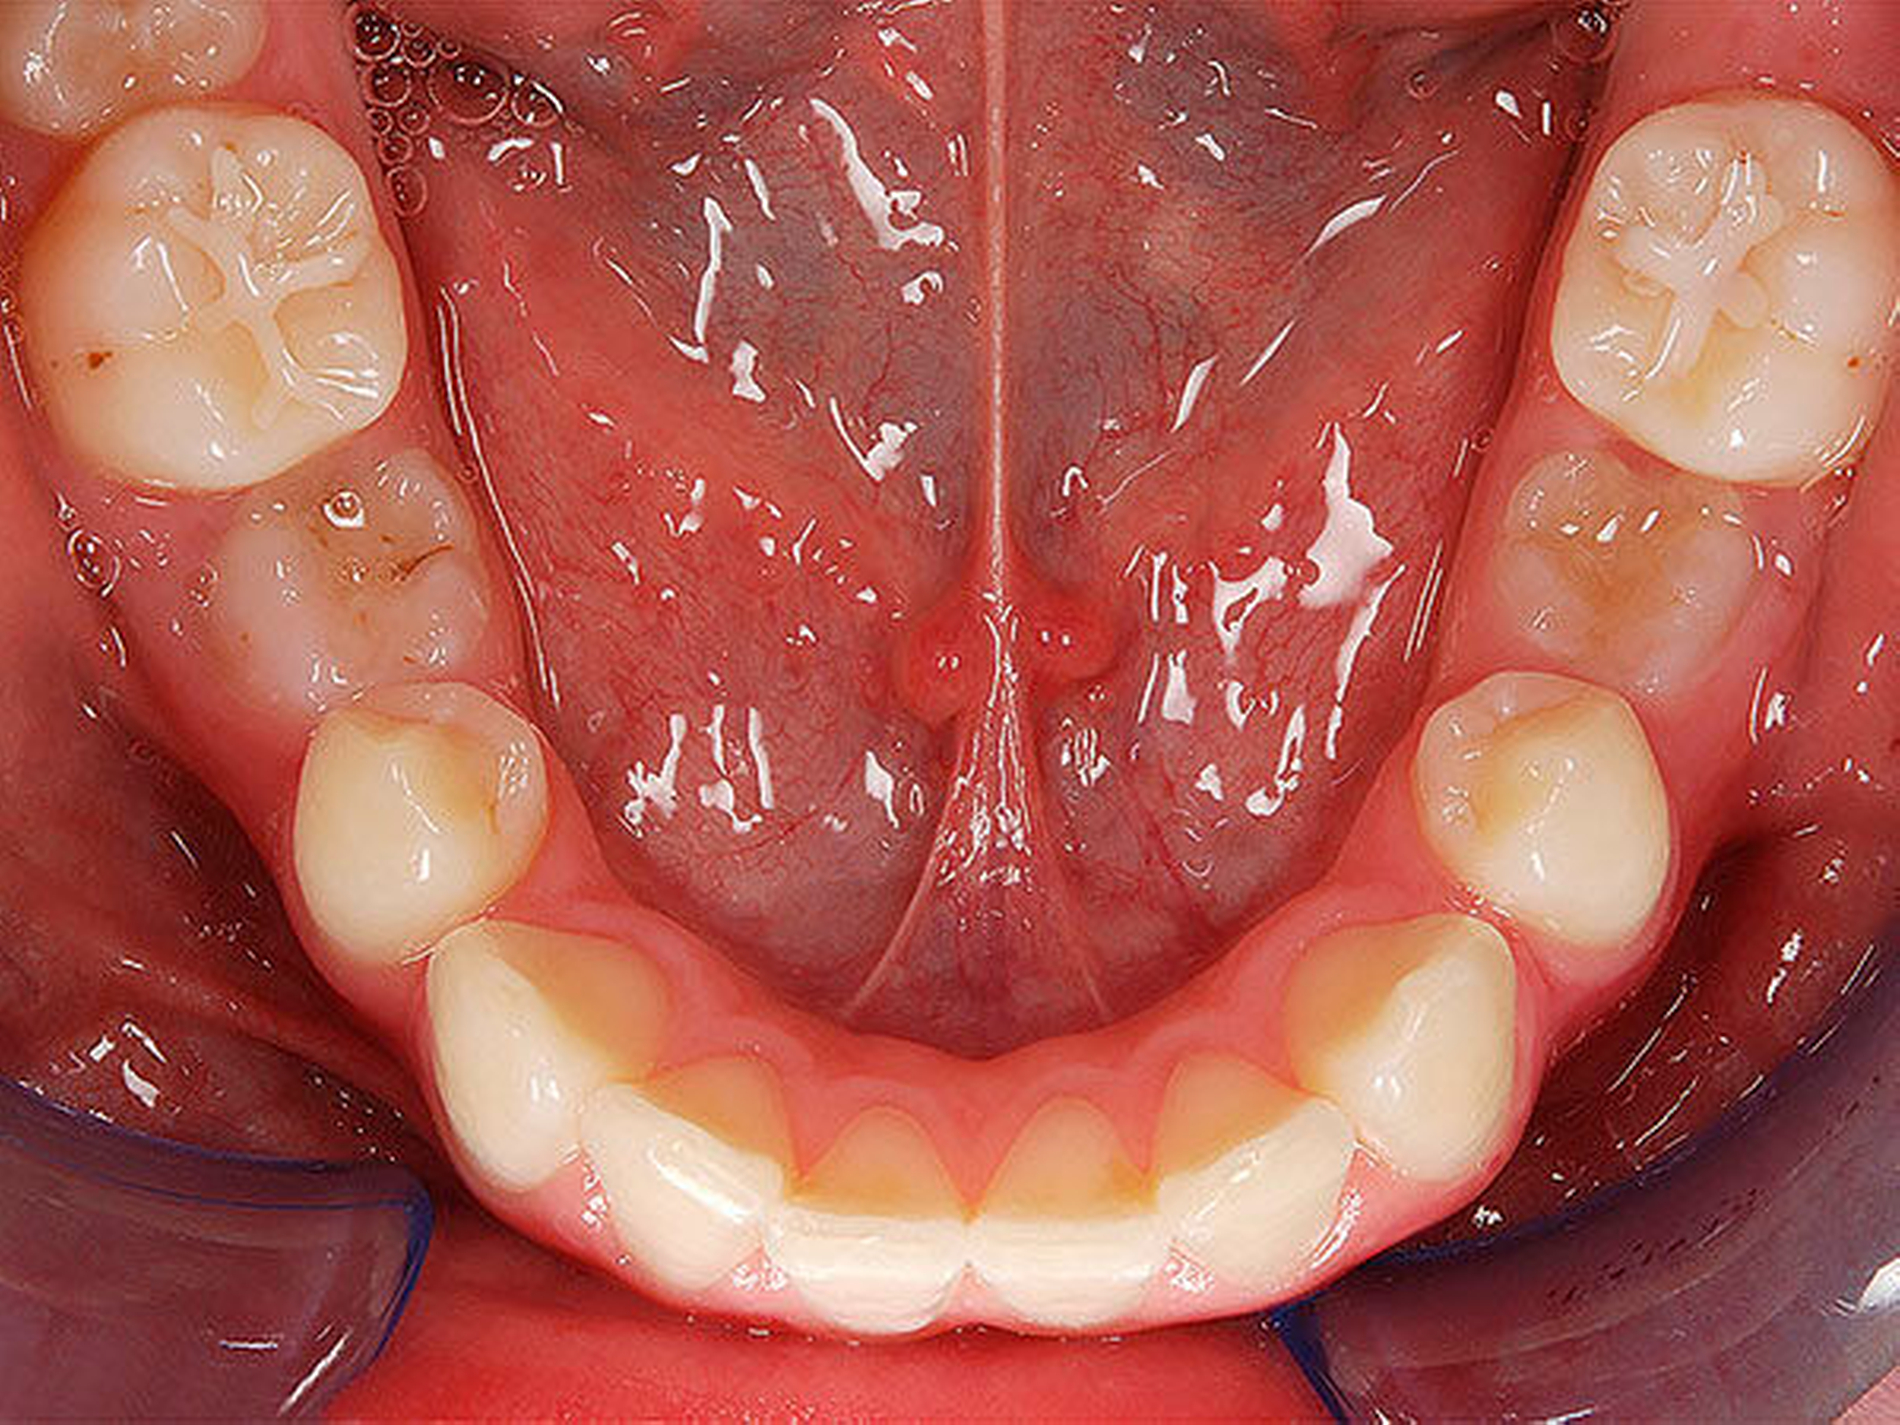

In der Gruppe des progenen Formenkreises werden Zahn- und Kieferfehlstellungen unterschiedlichster Ätiologie zusammengefasst. Diese können durch ein Missverhältnis im Wachstum beider Kiefer bedingt sein, das heißt durch Überentwicklung (Makro-/Prognathie) des Unterkiefers und/oder Unterentwicklung (Mikro-/Retrognathie) des Oberkiefers [Rakosi, 1989]. Besteht ein frontaler Kreuzbiss von Einzelzähnen oder einer ganzen Zahngruppe wird der Oberkiefer durch den Unterkiefer „eingefangen“, das heißt durch die palatinalwärts positionierten OK-Inzisiven wird das Oberkieferwachstum im Alveolarfortsatzbereich gehemmt sowie das Unterkieferwachstum „freigegeben“, da der Unterkiefer sich postnatal in sagittaler Richtung ohnehin stärker als der Oberkiefer entwickelt [Lux, 2004]. Zudem kann eine Zwangsbissführung des Unterkiefers nach ventral vorliegen [Keeling, 1998]. Diese kann zusätzlich zu einer unerwünschten Wachstumsstimulation des Unterkiefers mit nachfolgender skelettaler Manifestation führen. Mit einem therapeutisch eingestellten sicheren frontalen Überbiss (sagittal und vertikal) kann die weitere Kieferentwicklung koordinierter ablaufen (Abbildung 4). Die Anomalien des progenen Formenkreises besitzen häufig auch eine hereditäre Komponente, wobei unphysiologische Ruheweichteilbeziehungen oder Dysfunktionen den Phänotyp deutlich verstärken können. Da bei Klasse-III-Dysgnathien die skelettalen Therapieergebnisse bei frühzeitigem Behandlungsbeginn am besten sind, sollte frühzeitig mit einer kausalen Therapie begonnen werden – also sobald eine ausreichende Compliance des Patienten es zulässt, [Baccetti, 1998; Da Silva, 1998; Franci, 2004; Lang, 2001; Saadi, 2000].